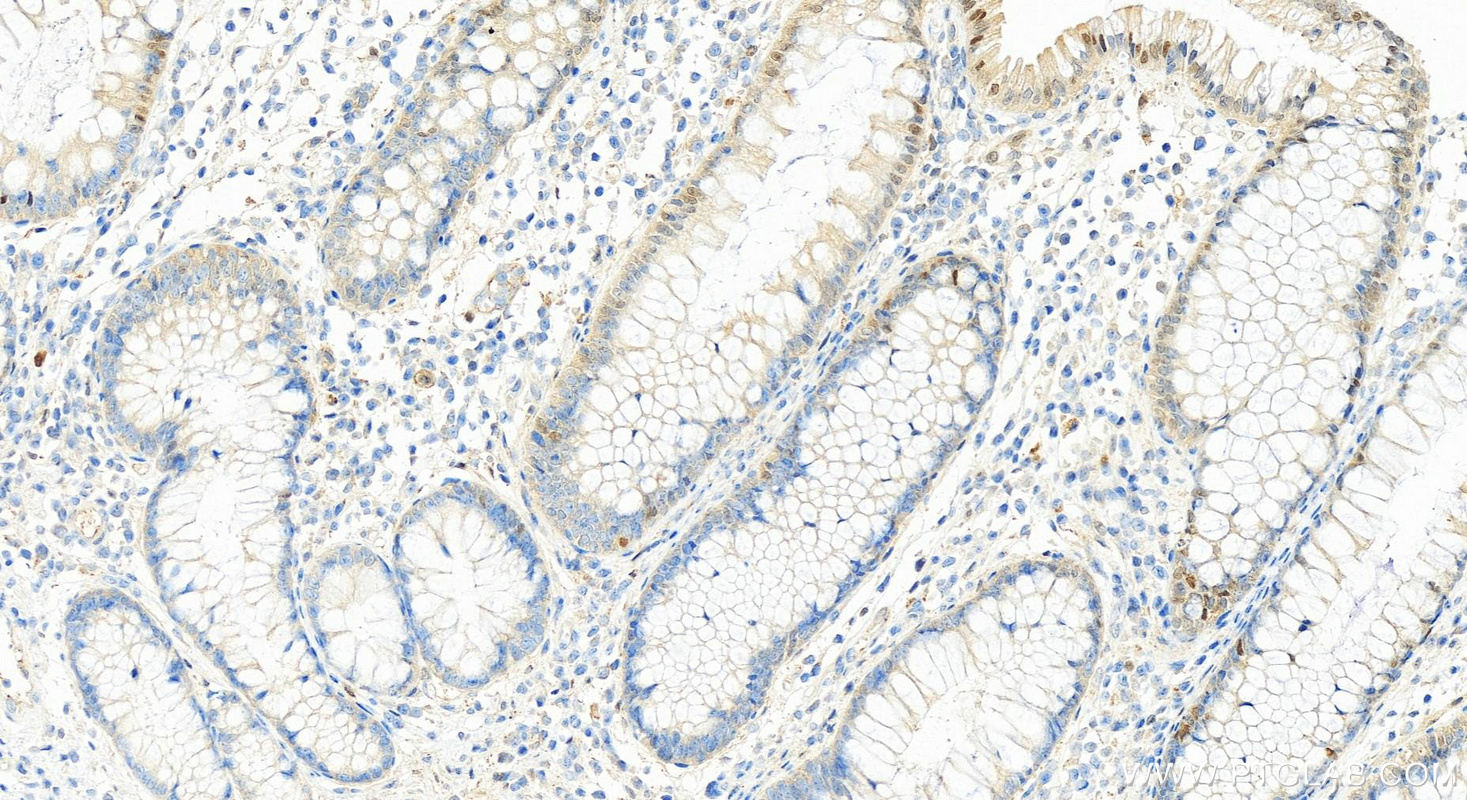

| Positive IHC detected in | human colon cancer tissue, human breast cancer tissue, human cervical cancer tissue, human kidney tissue, human stomach cancer tissue, human thyroid cancer tissue Note: suggested antigen retrieval with TE buffer pH 9.0; (*) Alternatively, antigen retrieval may be performed with citrate buffer pH 6.0 |

| Immunohistochemistry (IHC) | IHC : 1:5000-1:20000 |